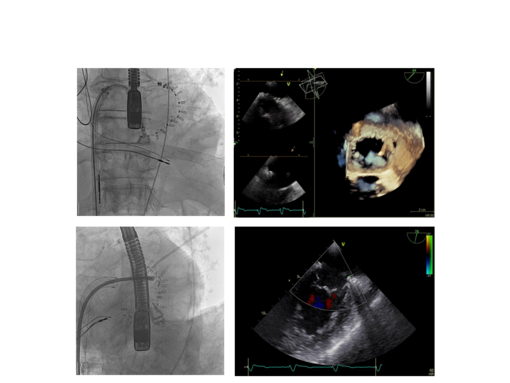

Daher stellt gerade für diese Patienten die kathetergestützte Mitralklappenrekonstruktion mit MitraClip eine mögliche und sinnvolle Therapieoption dar. Dieses Verfahren ist die derzeit am besten etablierte und am weitesten verbreitete Technik der interventionellen Therapie bei relevanter Mitralklappeninsuffizienz. Für den Eingriff, der unter Vollnarkose erfolgt, wird der MitraClip mithilfe eines Kathetersystems über die Leistenvene zum Herzen vorgeführt. Nach Punktion der Herzscheidewand erfolgt die Positionierung Befestigung des Clips (Klammer) an den beiden Segeln der Mitralklappe, wobei eine Doppelöffnung der Klappe erzielt wird. Die Klammer reduziert die Klappenundichtigkeit in der Regel deutlich, wobei in der Mehrzahl der Fälle ein oder zwei Clips und sehr selten drei Clips verwendet werden müssen.

Der Eingriff wird im Wesentlichen durch Ultraschall (Schluckechokardiographie) gesteuert. Die Gabe von Kontrastmittel ist nicht erforderlich. Nach dem Eingriff kommen die Patienten, meist bereits in wachem Zustand, für eine Nacht auf eine Überwachungsstation. Der gesamte Kliniksaufenthalt liegt bei unkompliziertem Verlauf zwischen 5 und 7 Tagen.